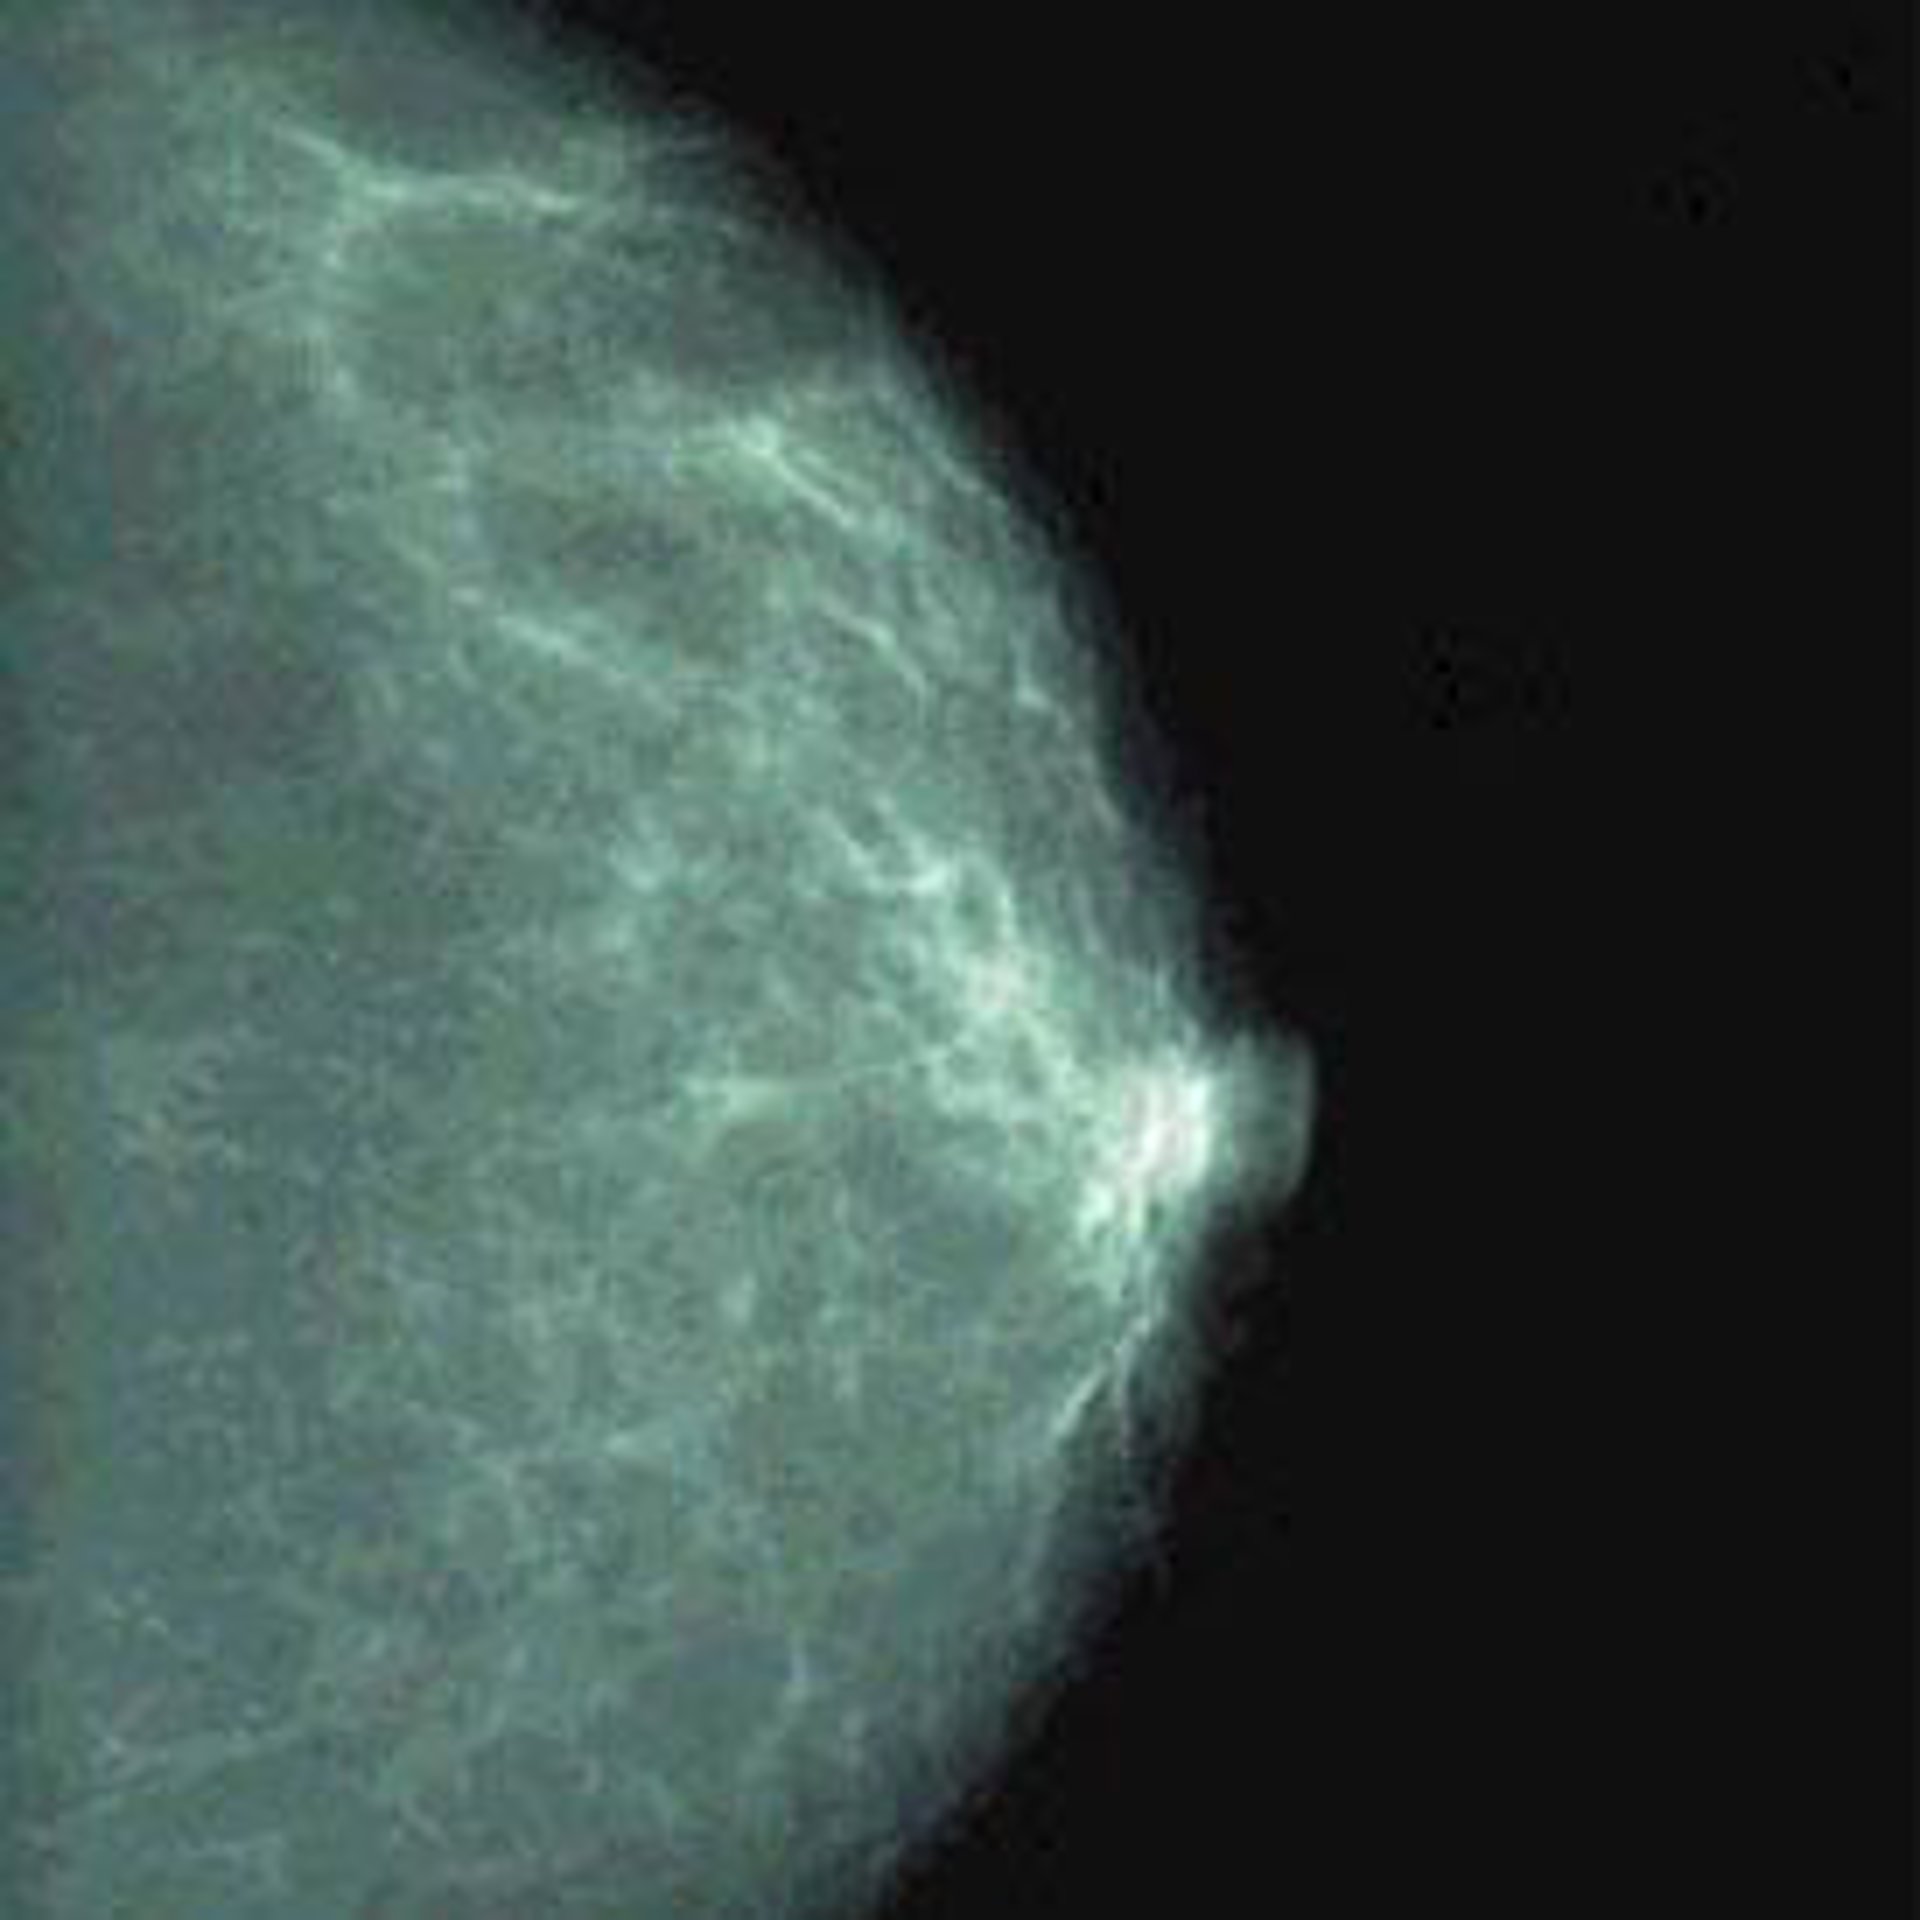

Precisamente con motivo del Día del Cáncer de Mama, la AECC ha lanzado la campaña 'En una mamografía se ve la vida', para animar a las mujeres en edad de riesgo a que participen en la campaña de detección precoz de este tipo de cáncer, conseguir detectar la enfermedad en su fase más temprana e incrementar la supervivencia por cáncer de mama en nuestro país.

La AECC recordó que las mujeres con edades comprendidas entre 45-50 y 65-70 años deben realizarse mamografías cada dos años, incluso aunque no presenten síntomas. "Sólo de esta manera es posible detectar una lesión tumoral en la mama, cuando todavía es demasiado pequeña para ser palpable y no ha invadido ganglios ni otros órganos", señaló.

Dado que el porcentaje de curación de los tumores de mama que se detectan en su etapa inicial (in situ) es superior al 95 por ciento, "la detección precoz es el arma más eficaz para luchar contra esta enfermedad", destacó la asociación. Recordó además que la mamografía permite detectar lesiones en la mama hasta dos años antes de que se hagan palpables, así como aplicar tratamientos menos agresivos.